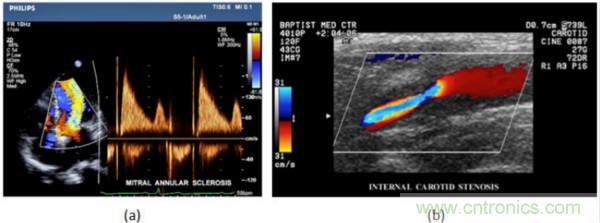

在CW和PW多普勒模式中,流信息是從一個聚焦聲束中獲得的,類似于A模式成像。在20世紀80年代,研究人員基于彩色多普勒技術完成了血流分布的二維信息可視化。彩色多普勒處理也是基于B模式/PW模式信號路徑。從感興趣區域收集多幀RF數據。由于感興趣區域中的血液流動導致圖像幀之間存在數據差異。相域中的自相關和時域中的互相關兩種算法可從RF數據中提取數據方差(即血流速度和方向信息):。根據預定義的顏色漸變條相應地映射包括速度和方向的血流信息。通常,藍色和紅色代碼分別識別朝向和遠離換能器移動的血流。當流速增加時使用更亮的顏色,反之亦然。顏色映射的2D分布始終疊加在B模式圖像上,以實時同時顯示個體解剖結構和血流。它對于診斷心血管疾病,如血管閉塞和心臟瓣膜反流,極其有用。典型的彩色多普勒圖像如下圖所示,(b)顯示頸動脈狹窄引起的血流流速變化。

超聲系統的信號鏈設計注意事項

圖7.彩色多普勒成像:(a)以彩色多普勒和CW模式獲得的圖像(由Philips提供); (b)顯示頸動脈狹窄的彩色多普勒(由GE提供)